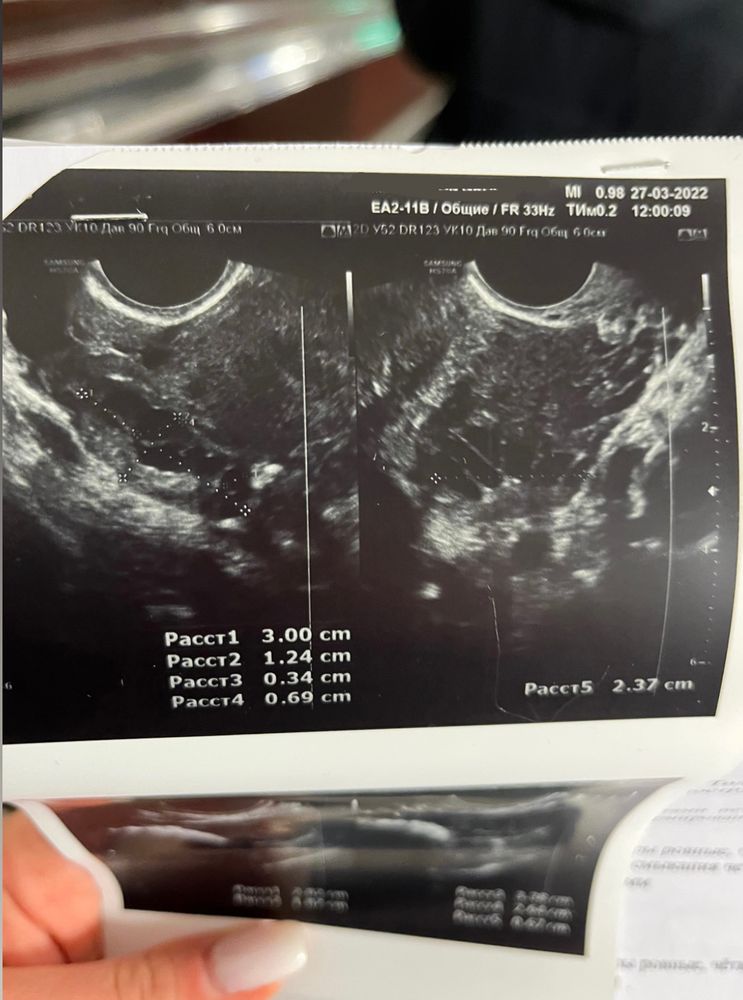

Здравствуйте! Ситуация следующая: с мужем начали практиковать ППА, потому что как говорится бояться уже нечего😂, но прямо планировать ещё рано, только начинаем вставать на ноги. Мы оба госслужащие, поэтому периодически проходим обследования общие, иногда сдаём кровь на ВИЧ, гепатиты. Поэтому за здоровье особо не переживали. М начались 4 марта, закончились 8 марта (всегда идут 4 дня). 3 ППА были с 11 по 13 марта, а 14 марта по моим ощущениям началась О. И вот где-то через неделю начинается самое веселое, частое чувство голода - то есть поем, а через 5 минут такое ощущение, что не ела неделю 🙈 усилилось обоняние, с каждым днём нарастало чувство слабости. Я уже думала, всё, ОНО😍😂 и за неделю (и 2 дня) до начала М начинает тянуть и подергивать левый яичник, иногда потягивает правый. Я пошла на узи малого таза…ожидала услышать что-то конкретное, но врачи сказали наблюдать дальше за состоянием и в случае задержки делать тест, а так, из того, что они увидели: что-то у меня там лопнуло (боюсь неправильно назвать) и произошло кровоизлияние в брюшную полость (большое темное пятно в нижней части, на снимке матки), а боль в левом яичнике обусловлена наличием в нем желтого тела. В общем как-то так. Сейчас уже 4-ый день задержки, левый яичник все также потягивает вечерами, сохраняется слабость и сонливость. Утром сегодня делала тест - кристально чистый, ни намёка на призрака. Подскажите, пожалуйста, в моем случае, я так понимаю, уже можно исключать беременность? Что это может быть? Фото снимков с УЗИ прилагаю (сделаны на 24 ДЦ). Заранее спасибо!